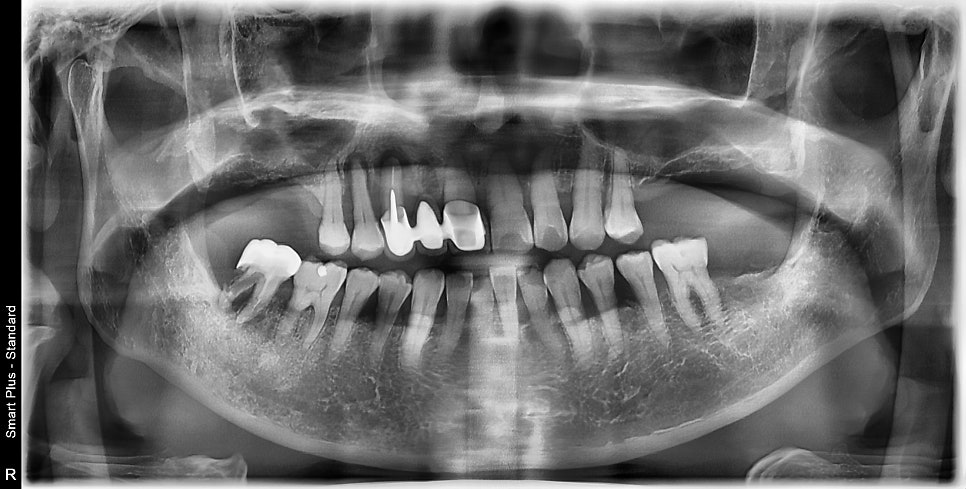

전반적으로 봤을 때 위턱뼈의 어금니 다수가 빠진 상태이고

남아있는 몇몇의 치아 주변에서 염증소견이 보입니다

아래쪽은 괜찮으신데 위쪽 치아가 흔들리고 잇몸이 부어있어서

임플란트 치료에 대해 설명을 원하셨습니다.